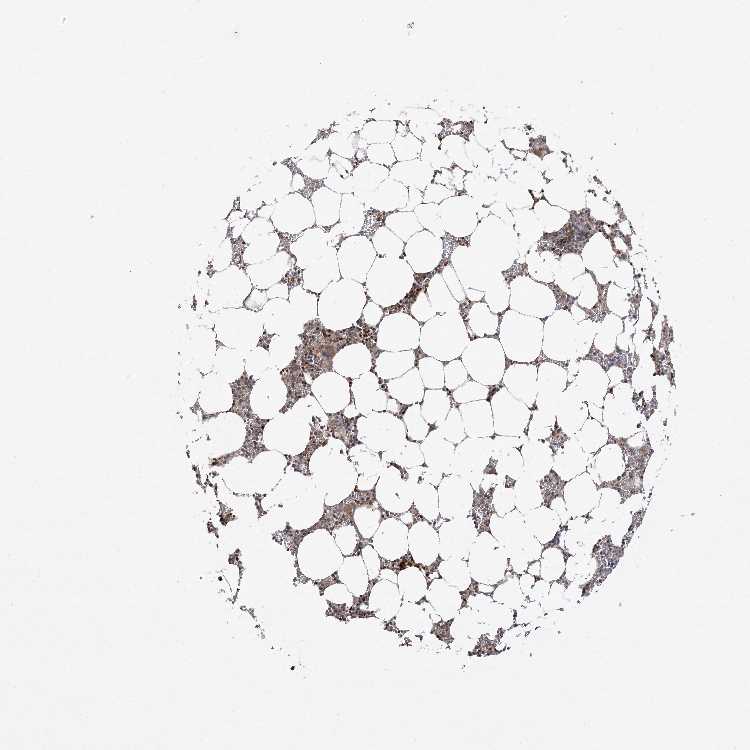

BONE MARROW - Antibody stainingi

Antibody staining in the annotated cell types in the current human tissue is reported as not detected, low, medium, or high, based on conventional immunohistochemistry profiling in selected tissues. This score is based on the combination of the staining intensity and fraction of stained cells.

Each image is clickable and will lead to virtual microscopy that enables deeper exploration of all samples and also displays staining intensity scores, fraction scores and subcellular localization as well as patient and tissue information for each sample.

Antibody HPA036698Antibody HPA036699

Hematopoietic cells LowLow